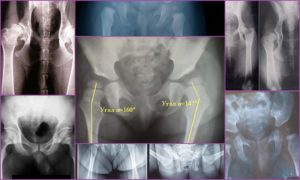

Рентгенологические критерии дисплазии:

1. Ацетабулярный индекс, предназначенный для оценки величины отклонения между крышей впадины и головкой бедренной кости. На снимке выявляется путем построения двух линий – касательной к вертлужной впадине, вторая – соединяется у-образные хрящи с обеих сторон. Нормальное значение – 12-16 градусов; 2.

Шеечно-диафизарный угол – это величина, определяющая возможное искривление впадения головки путем построения касательных между диафизом и шейкой; 3. Угол вертикального соответствия определяется путем построения линий по касательной к вертлужной впадине, продольной осью шейки кости. У детей старшего возраста показатель – 85-90%; 4.

Степень покрытия определяется по линии, опущенной вниз от латеральной части крыши. Для оценки требуется визуализация расположения головки бедра. В норме у детей 6 лет верхняя часть бедренной кости покрывается на ¾; 5. Симптом Омбредана применяется для выявления диспластических изменений у малых детей.

Если провести перпендикуляр от наружной части вертлужной впадины и соединить горизонтальной линией у-образные хрящи, то в норме точки окостенения располагаются в нижне-внутреннем квадранте; 6. Центрация головки бедра определяется продолжением оси шейки бедренной кости на крышу впадины.

В норме линия находится на границе между наружной и передне-средней частью. Показатель позволяет выявить переднюю или заднюю децентрацию; 7. Поправки на приведение, отведение изучаются путем проведения линий, которые соединяют оси бедренных костей с горизонталями по шейке.

Коррекция продольной оси шейки бедра проводится на угол, полученный при сравнении перпендикуляра диафиза с полученным перпендикуляром;

8. Величина физиологического дефицита определяется наличием или отсутствием ядер окостенения, которые должны быть по возрастным особенностям.

Разметка фото тазобедренных суставов в норме и при дисплазии

Для выявления этих нарушений по рентгенограммам рекомендуются снимки, выполненные в крестцово-вертлужных, аксиальной, задней проекции. После графической разметки рентгенограммы тбс специалисты определяют децентрацию и вывихи. Задняя проекция позволяет выявить нарушения во фронтальной проекции.

Критерии выявления нестабильности не требуются серьезных графических корректировок. Простая разметка позволяет выявить вышеописанные критерии. При расшифровке заключения требуется отметить на фото погрешности укладки.

Достаточно продолжить на рентгенограмме продольную ось шейки бедренной кости к крыше впадины, чтобы предположить правильность соотношения суставных поверхностей тбс.

При децентрации перпендикуляр расположен в медиальной части, но не во внутренней.

При подвывихе – осевая линия находится в наружной трети. Полный вывих определяется по выходу перпендикуляра шейки за наружную часть крыши.